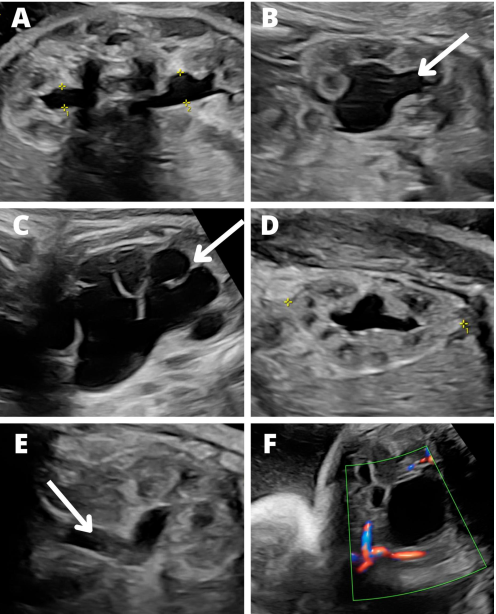

Prenatal ultrasound parameters of the UTD classification. (A) APRPD; (B) calyceal dilation, arrow indicates a dilated calyx;

(C) kidney parenchyma thickness, arrow points at the abnormally thin parenchyma in a fetus with severe UTD at 37 weeks of gestation; (D) the

appearance of the parenchyma, an example of normal echogenicity and corticomedullary differentiation at 34 weeks of gestation; (E) ureter

dilation (arrow) at 34 weeks of gestation; (F) normal bladder and amniotic fluid. APRPD, anterior-posterior renal pelvic diameter; UTD, urinary

tract dilation.